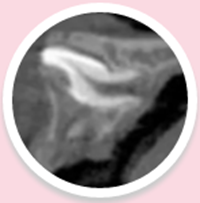

CBDT顯示:恒牙牙胚旋轉90度,牙根開始彎曲發(fā)育:

4.png

慶幸的是欣欣這顆牙齒根尖口未完全閉合,呈喇叭口樣,我們可以用正畸的方式試著來牽引,改變牙冠的方向,讓牙根繼續(xù)按正常的位置發(fā)育!